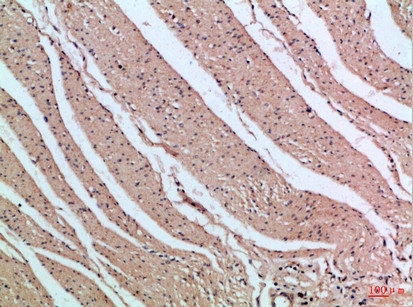

Immunohistochemical analysis of paraffin-embedded Human-colon, antibody was diluted at 1:100